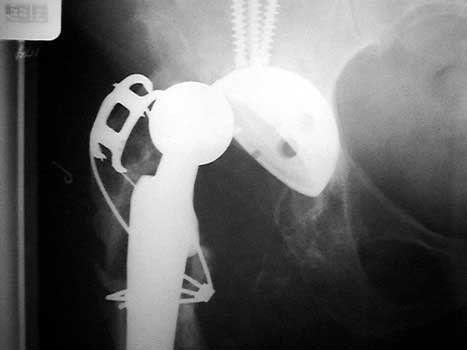

Dislocated femoral component secondary to loose acetabular cup

with reverse acetabular inclination